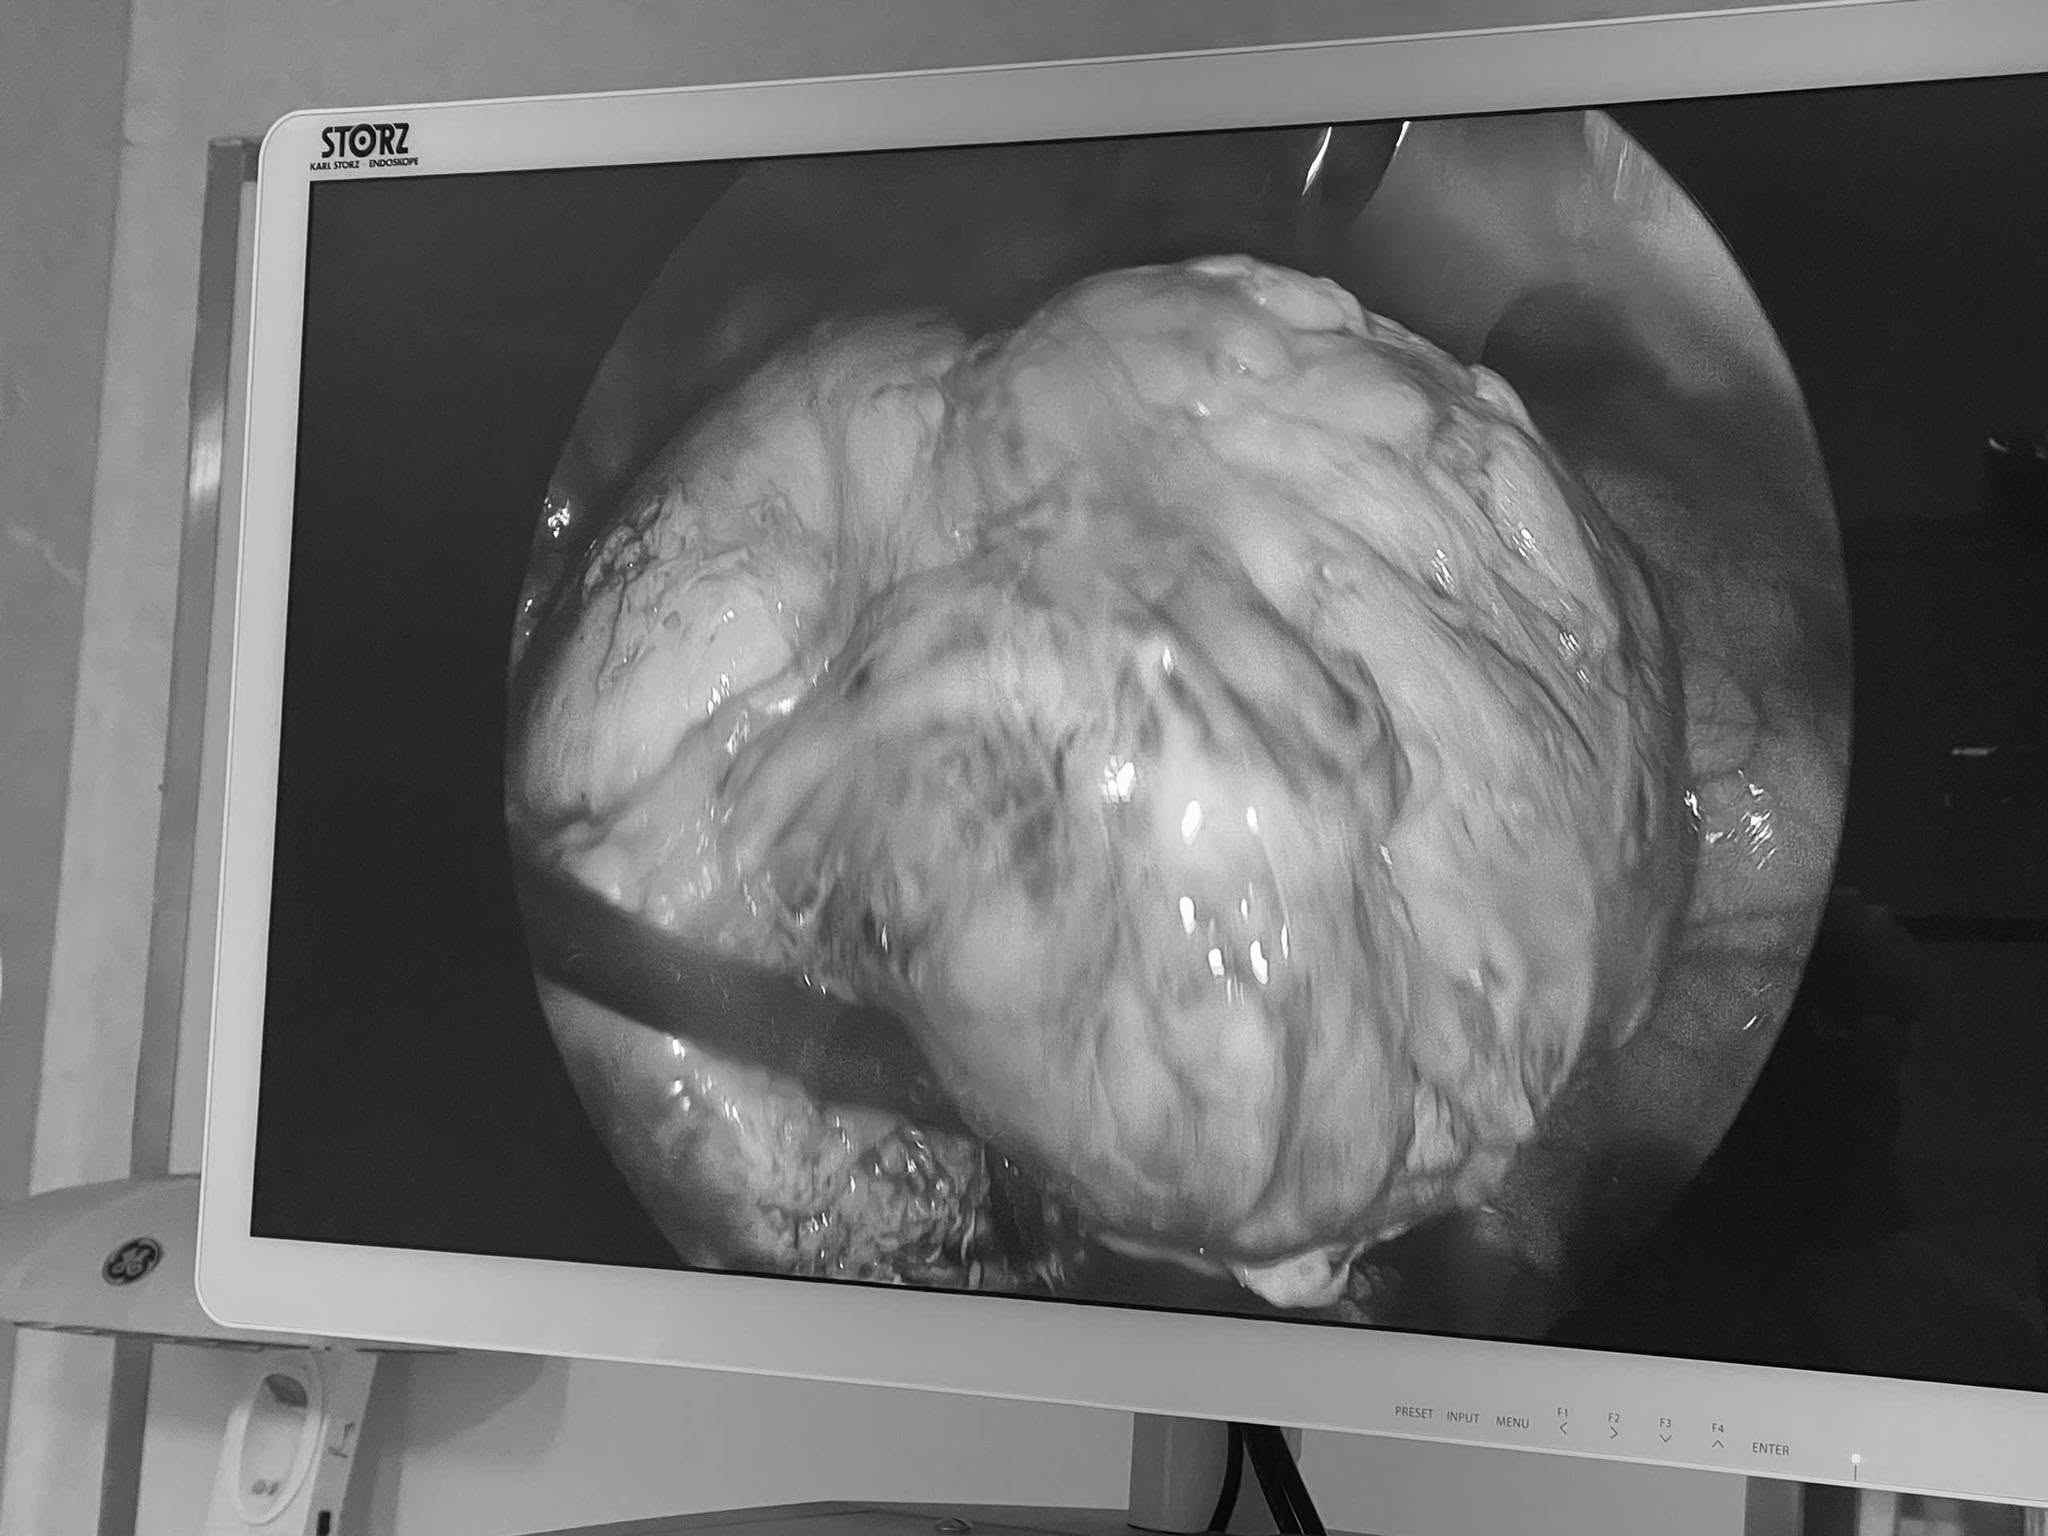

Almost lost motherhood due to giant uterine fibroids

|

A 31-year-old patient with prolonged menstruation and severe anemia due to a uterine fibroid of more than 10cm was successfully removed by endoscopic surgeons.